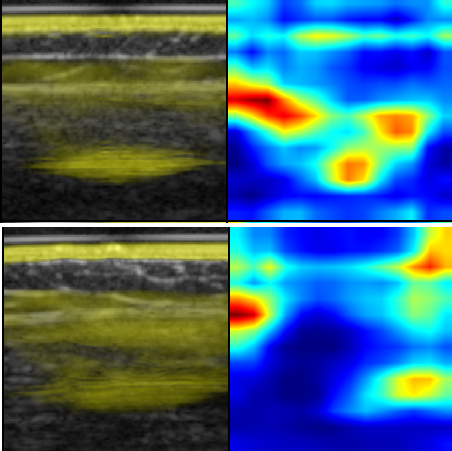

Neuromuscular diseases (NMDs) cause a significant burden for both healthcare systems and society. They can lead to severe progressive muscle weakness, muscle degeneration, contracture, deformity and progressive disability. The NMDs evaluated in this study often manifest in early childhood. As subtypes of disease, e.g. Duchenne Muscular Dystropy (DMD) and Spinal Muscular Atrophy (SMA), are difficult to differentiate at the beginning and worsen quickly, fast and reliable differential diagnosis is crucial. Photoacoustic and ultrasound imaging has shown great potential to visualize and quantify the extent of different diseases. The addition of automatic classification of such image data could further improve standard diagnostic procedures. We compare deep learning-based 2-class and 3-class classifiers based on VGG16 for differentiating healthy from diseased muscular tissue. This work shows promising results with high accuracies above 0.86 for the 3-class problem and can be used as a proof of concept for future approaches for earlier diagnosis and therapeutic monitoring of NMDs.